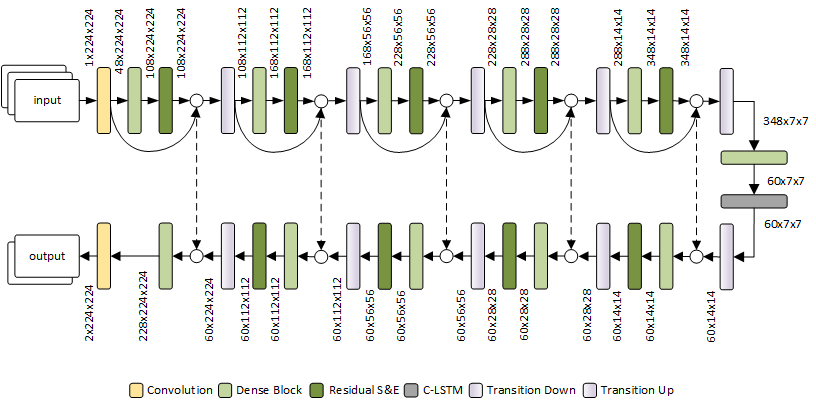

COVID-19 infection caused by SARS-CoV-2 pathogen is a catastrophic pandemic outbreak all over the world with exponential increasing of confirmed cases and, unfortunately, deaths. In this work we propose an AI-powered pipeline, based on the deep-learning paradigm, for automated COVID-19 detection and lesion categorization from CT scans. We first propose a new segmentation module aimed at identifying automatically lung parenchyma and lobes. Next, we combined such segmentation network with classification networks for COVID-19 identification and lesion categorization. We compare the obtained classification results with those obtained by three expert radiologists on a dataset consisting of 162 CT scans. Results showed a sensitivity of 90\% and a specificity of 93.5% for COVID-19 detection, outperforming those yielded by the expert radiologists, and an average lesion categorization accuracy of over 84%. Results also show that a significant role is played by prior lung and lobe segmentation that allowed us to enhance performance by over 20 percent points. The interpretation of the trained AI models, moreover, reveals that the most significant areas for supporting the decision on COVID-19 identification are consistent with the lesions clinically associated to the virus, i.e., crazy paving, consolidation and ground glass. This means that the artificial models are able to discriminate a positive patient from a negative one (both controls and patients with interstitial pneumonia tested negative to COVID) by evaluating the presence of those lesions into CT scans. Finally, the AI models are integrated into a user-friendly GUI to support AI explainability for radiologists, which is publicly available at http://perceivelab.com/covid-ai.